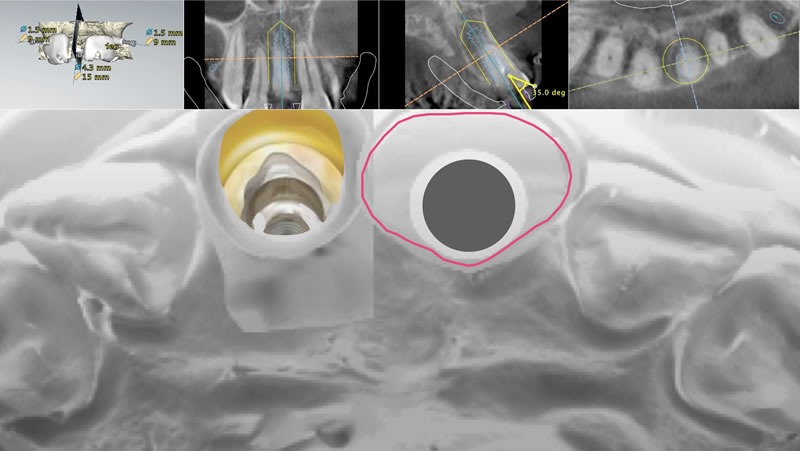

ワックスアップ、ラジオグラフィックガイドからCTスキャン

Nobel Clinician による埋入位置・角度のプランニング